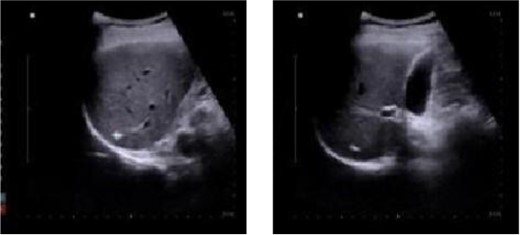

A 50-year-old male patient is diagnosed with mixed hemorrhoid. He reported no prior medical history of hypertension; diabetes; cardiovascular, pulmonary, hematological disorders. The patient’s symptom was the prolapse of the anal mass after each stool and lasted for >2 years. Proctoscopy revealed the presence of two large external hemorrhoids with three internal hemorrhoids in the 3, 7, and 11 o’clock position. The patient underwent hemorrhoidectomy under combined lumbar epidural anesthesia. The surgery went smoothly. Unfortunately, on the second day post-surgery, the patient developed sudden chills and fever, with a body temperature of 39.9°C. Urgent investigations revealed the following: routine blood analysis showed white blood cells at 13.28 × 10^9/L, platelets at 307 × 10^9/L, lymphocyte percentage at 8.1%, and neutrophil percentage at 89.2%. The patient received intramuscular lyserpyrine injection (0.9 g), fluid rehydration, and physical cooling. Consequently, the patient’s body temperature decreased to 37°C. On the third morning post-surgery, the body temperature rose to 38.5°C. Further routine blood analysis revealed the following critical values: white blood cell count, 35.3 × 10^9/L, lymphocytes, 1.9%; and neutrophils, 95.2%. Examination of the wound tissue revealed no purulent exudate. The patient reported upper abdominal pain accompanied by nausea and reduced appetite. A prompt abdominal color ultrasound examination indicated a cystic solid echo near the right lobe of the liver, adjacent to the diaphragmatic apex, measuring ~29 × 26 mm, with indistinct borders. The diagnostic impression from the abdominal color Doppler ultrasound suggested a hepatic abscess (Fig. 1).

Abdominal color ultrasound findings on the third day after surgery.